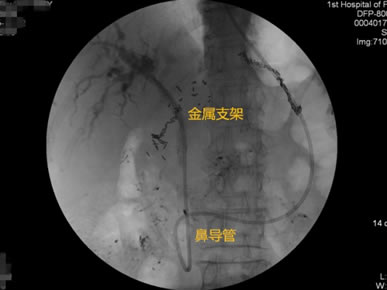

胃毕-Ⅱ术后乳头倒置 胃毕-Ⅱ术后胰管胆管双支架植入 胃毕-Ⅱ术后金属支架植入

胃毕-Ⅱ术后胰管胆管双支架植入 胃毕-Ⅱ术后胆管金属支架植入